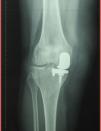

A 72-year-old woman who had undergone unicompartmental arthroplasty in right knee 12 years earlier, presented with a 6-month history of pain in that knee, in the absence of fever or systemic symptoms. On physical examination, the knee was found to be swollen. Radiography revealed a prosthesis in the medial compartment, which remained unchanged since the partial knee replacement (Fig. 1). Arthrocentesis yielded a dark fluid (Fig. 2) with 150 white blood cells/μL (75% polymorphonuclear cells), glucose level at 90mg/dL and proteins at 2mg/dL. Culture of the joint fluid was negative. With the suspicion of metallosis, the patient was referred to the orthopedics department and underwent total knee replacement. The pathological study of a specimen of synovial tissue showed macrophages with a blackish pigment in the cytoplasm and lymphocytes (Figs. 3 and 4). At the present time, the patient is asymptomatic.

Metallosis is defined as a corrosion due to the erosion of metallic components, which produces particles that induce a hypersensitivity reaction. It is generally asymptomatic and the development of pain or stiffness is due to the secondary loosening of the prosthesis.1 It may be suspected when lobulated osteolytic areas, with or without increased volume of the adjacent soft tissues, are detected on plain radiography. The differential diagnosis should include aseptic dislocation of the prosthesis and septic arthritis.2 Macroscopic examination shows a black pigmentation of the joint, together with a dark-colored synovial fluid. A microscopic study reveals metallic particles, either free or engulfed by macrophages, with a lymphocytic infiltrate that suggests an immune response.3 Treatment consists in replacement of the prosthesis and performance of synovectomy for the purpose of eliminating the metallic particles.3